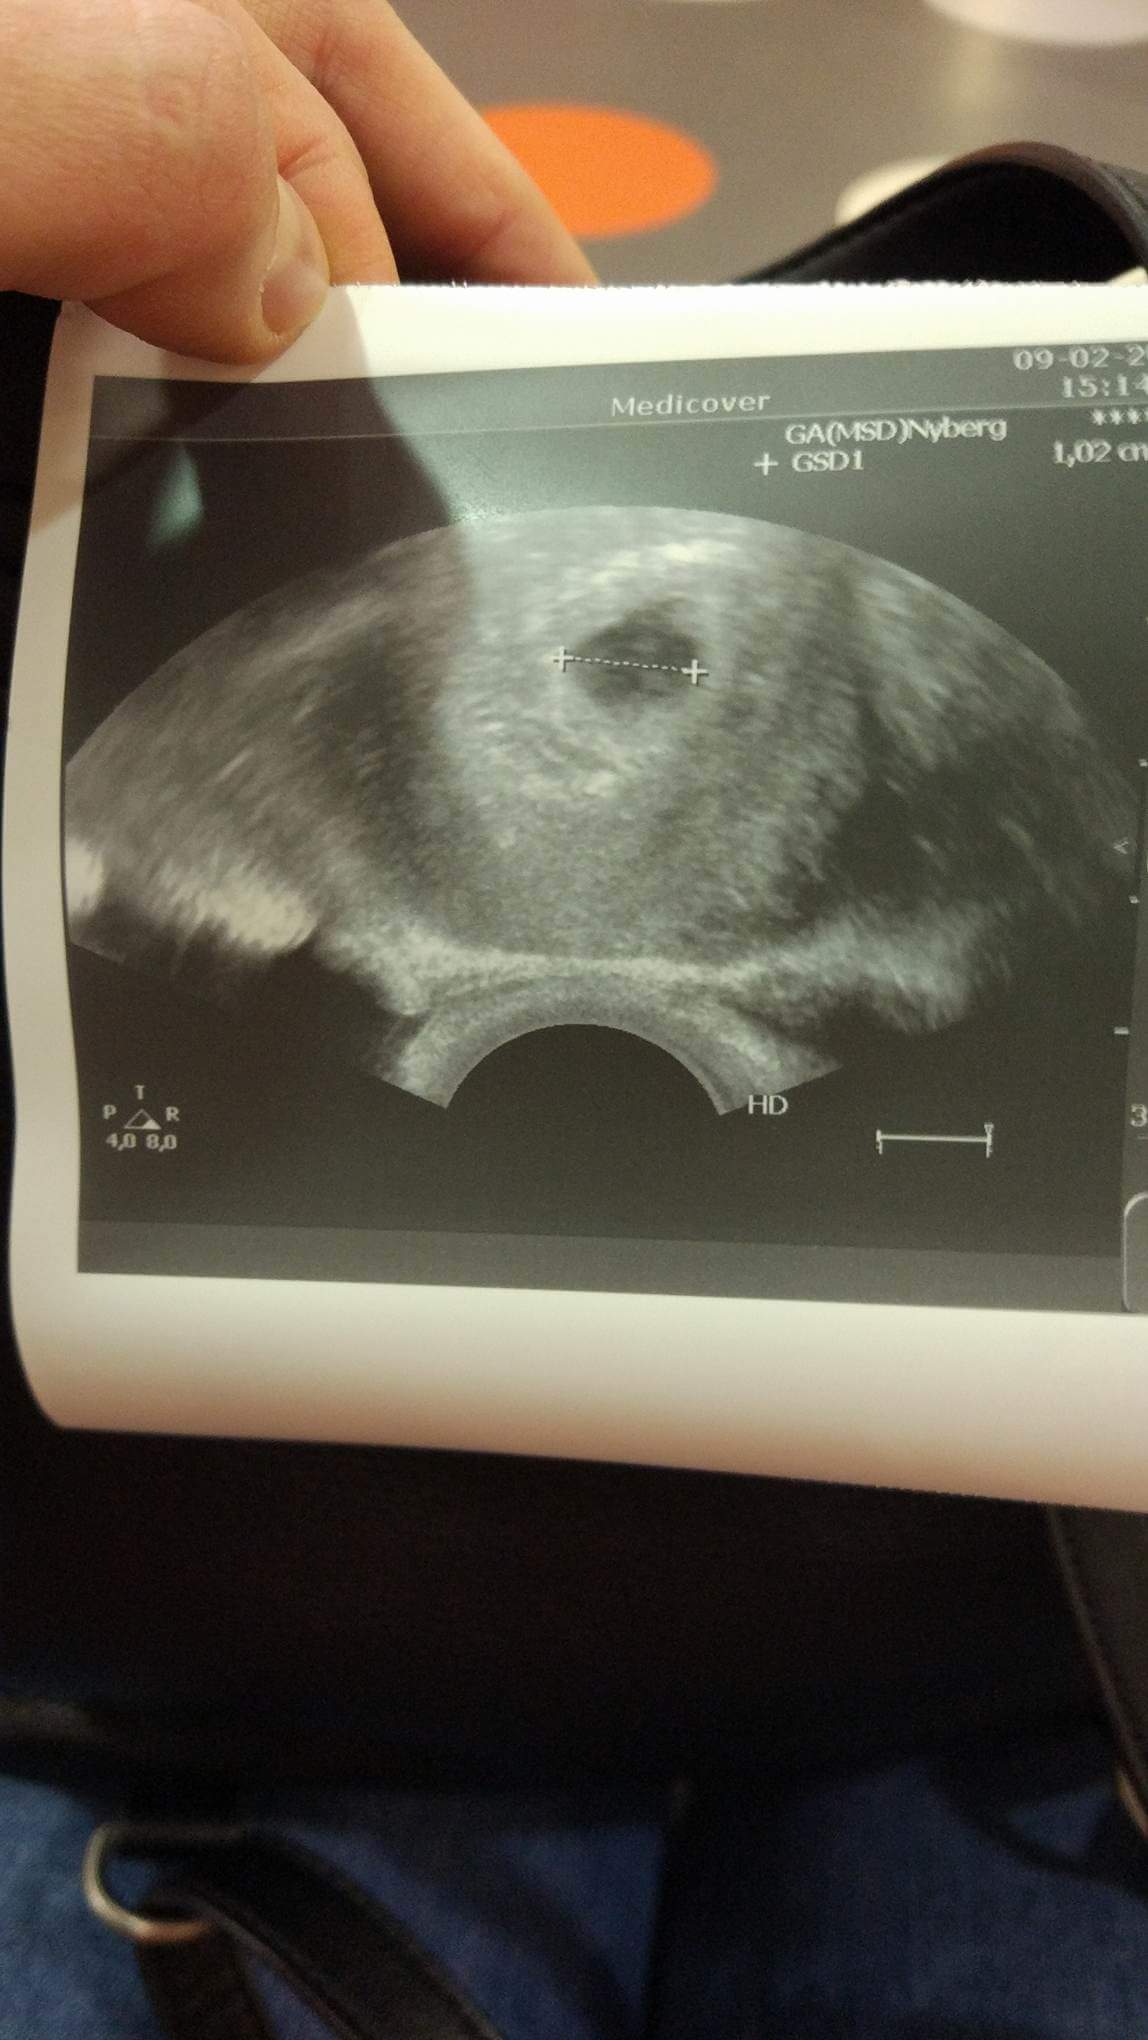

Cześć a ja dzisiaj byłam u ginekologa, zrobił USG dopochwowe, potwierdził ciążę wszystko jest ok , z USG wyszło 6 t i 3 dni widziałam już serduszko , ale lekarz powiedział że jeszcze nie będziemy słuchać. Następną wizytę mam 1 marca i wtedy też dostanę skierowania na badania kazał przyjmować witaminy. Pozatym dopadły mnie mdłości co dwie godziny jem ,

Cześć dziewczyny ! To i ja się pochwalę .. pierwszy cykl i złoty strzał . Termin mam na 14 października.

Załączniki

• received_10204113079705087.jpeg

received_10204113079705087.jpeg

137,7 KB · Wyświetleń: 146